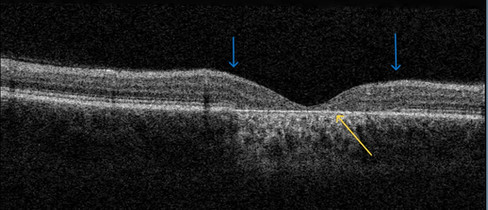

Hastanın her iki gözünün OCT incelemesinde renkli resimde gördüğümüz keskin sınırlı atrofinin OCT de de izlendiği görülüyor. OCT lerde ISOS bandı (veya EZ), RPE ve fotoreseptör iç tabakalarının mavi oklarla işaretlenen bölgeye geldiği zaman bıçıkla kesilir gibi aniden kaybolduğu gözlenmektedir. Bu tabakaların kaybolmasına bağlı olarak lezyonun orta bölgelerinde retinanın adeta aşağıya doğru "çöktüğü" görülüyor. Bu bu bölgedeki dokuların atrofisine bağlı... Sarı okla işaretlenen çizgi Bruch membranı ve üzerinde yer alan RPE kalıntıları ve fibrozise bağlı olarak biraz kabalaşmış olarak izleniyor. Üzerindeki RPE atrofiye uğramış ve geriye sadece Bruch membranı kalmış ve üzerinde yer alan atrofi alanı ile tam bir uyumluluk gösteriyor, yani önce RPE atrofiye gitmiş ve sonrasında ona bağlı fotoreseptör hücreleri de bölgesel olarak atrofiye gitmiş.

Bu hastalarda tanı koyduran en önemli bulgu makülada böyle keskin sınırlı bir atrofi olmasıdır. Hasta ve sağlıklı retina bu hastalarda çok keskin sınırlarla birbirinden ayrılır.